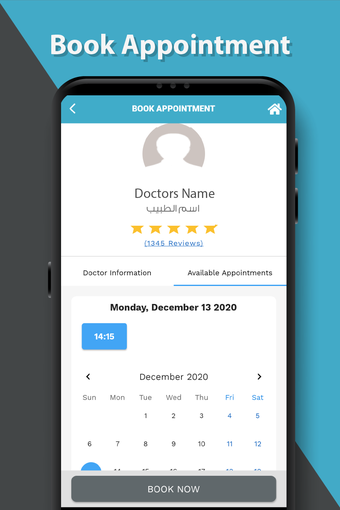

これは、Dr. Sulaiman Al-Habib Medical Services Groupが提供するすべてのサービスにアクセスするのを助ける無料のアプリです。グループの持続的なデジタル変革の重要な部分であり、効率と生産性の向上を重視しています。この新しいアプリは、オンライン医師相談から医療検査や放射線学の報告書まで、グループが提供するすべてのサービスに簡単にアクセスできるようになります。また、あなたと家族の医療記録を閲覧する機会も提供しています。